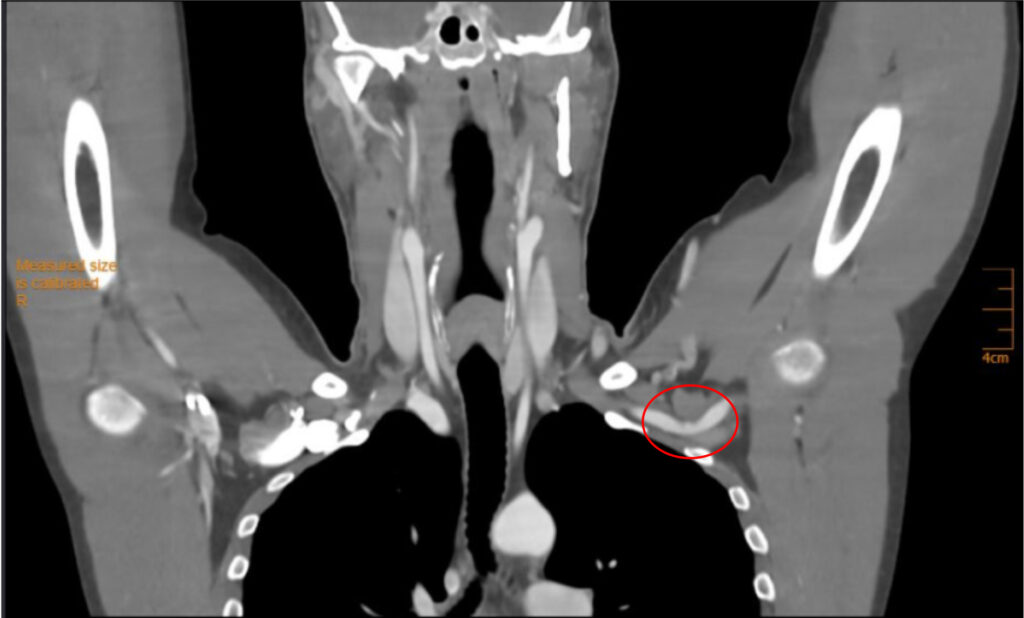

Im vorliegenden Fall des 39-jährigen Tennisspielers konnte ein neurogenes TOS ausgeschlossen werden. Eine CT-Angiographie unter Provokationsstellung konnte das duplexsonographisch vermutete arterielle TOS bestätigen. Das arterielle TOS repräsentiert mit 1 % die seltenste der drei TOS-Entitäten (neurogen, venös, arteriell). In den Händen von erfahrenen TOS-Chirurgen widerspiegelt die operative Dekompression mit einem transaxillären Zugang den therapeutischen Goldstandard, wobei mit einem medianen «Return-To-Sports» von 9 – 10 Monaten gerechnet werden muss. Gemäß amerikanischen Daten erreichen betroffene Baseball-Pitcher auch drei Jahre nach operativer Dekompression wieder präoperative maximale Wurfgeschwindigkeiten von rund 150 km/h [2].

M. pectoralis minor (M. pectoralis minor Syndrom).